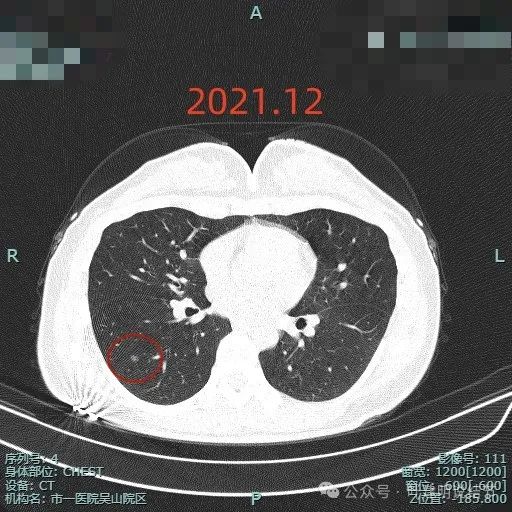

病史摘要:患者主因“检查发现肺部阴影5年”就诊。5年前当地医院体检胸部CT提示肺部结节,无明显症状未治疗。2024年11月杭州市肿瘤医院复查胸部CT,右肺多枚小结节,LUNG-RADS 2,建议年度随诊。现患者无不适,为求进一步诊治入院。起病以来,患者神志清,精神、胃纳、睡眠、二便正常,体重无明显变化。诊疗过程:体格检查未提及。多次胸部CT显示右下叶磨玻璃结节,轮廓与瘤肺边界清楚,

肺不典型增生

典型